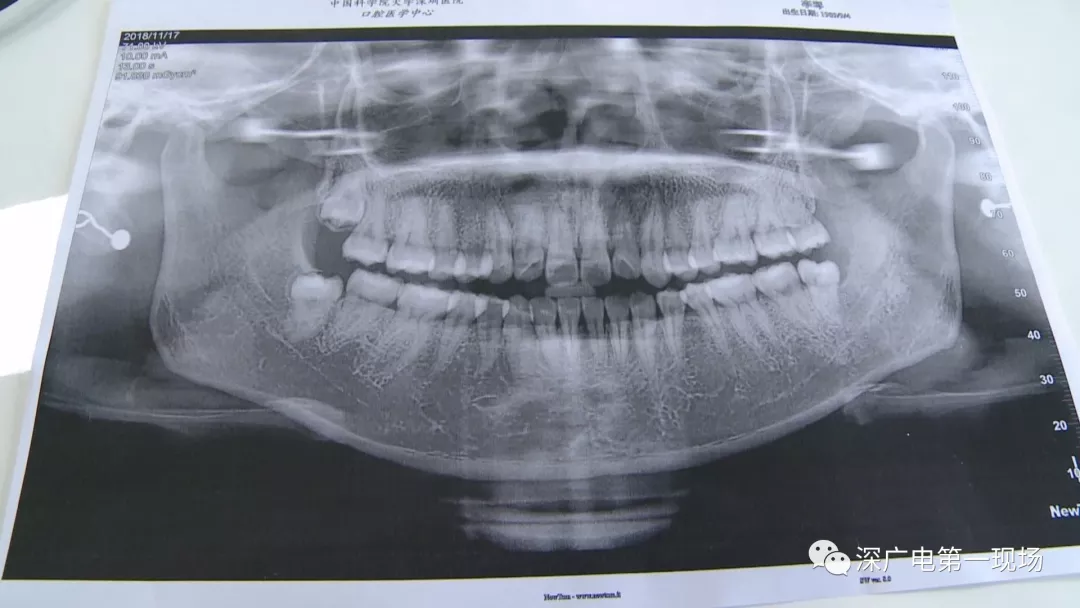

中國科學(xué)院大學(xué)深圳醫(yī)院口腔科主任賈岳介紹,對于不同患者的牙齒,它的治療方法都不一樣,所以不同牙齒,醫(yī)院收費的標準也各不相同。牙齒的治療方案,都是根據(jù)患者牙齒具體情況來制定,然后再去收費,同時也會參考病人實際情況來做不同的治療項目。